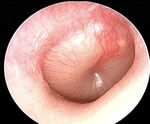

Review: Otoscopy Examples of Abnormal TMs

Normal Otoscopic Exam Findings:

• Tympanic membrane (TM) should be intact and

appear pearly grey or whitish/pinkish grey

Bulging, red TM - Acute Otitis Media Cholesteatoma

Normal TM – Right Side

Pars flaccida

Lateral/short process of malleus

Incus Manubrium of malleus

Umbo Otitis media with effusion Myringosclerosis

Cone of light

Pars tensa

Annulus

Hemotympanum Retracted TM

Back